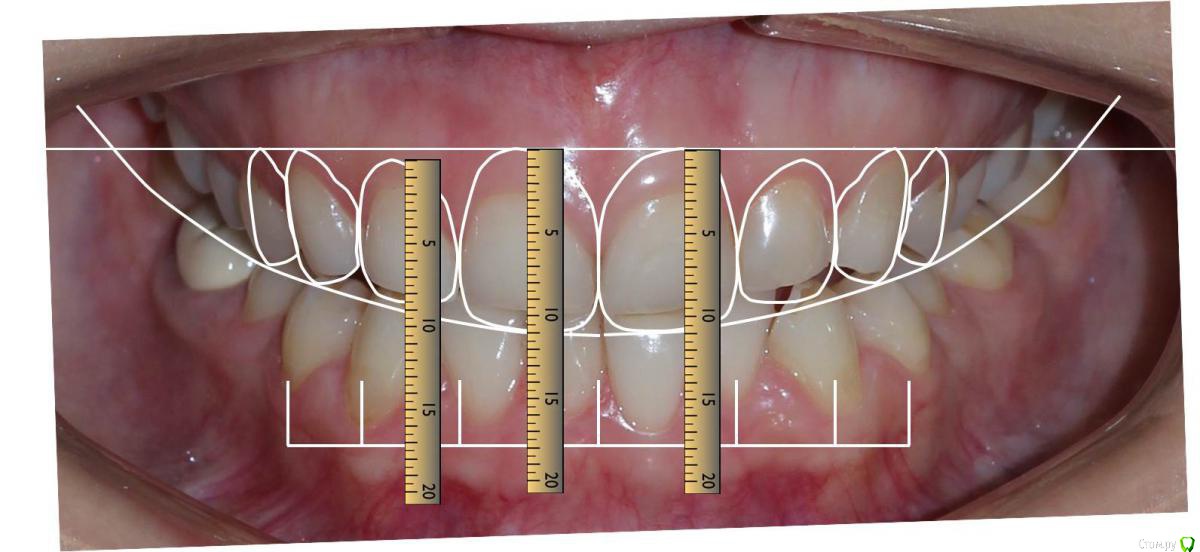

Сева северный Опубликовано 9 декабря, 2015 Поделиться Опубликовано 9 декабря, 2015 Ко мне обратилась молодая девушка, не довольная своей улыбкой. Был проведен этап планирования.... анализ улыбки ..(DSD), (wax up) и примерка (mock up)Проведенный этап...с мотивировал пациентку . 15 Ссылка на комментарий

Сева северный Опубликовано 11 декабря, 2015 Автор Поделиться Опубликовано 11 декабря, 2015 Почему не через зеркало?В принципе на вопрос уже ответили.... могу лишь добавить, что при (wax up) мы как правило воск добавляем, причем его слои, не всегда одинаковой толщины, поэтому темные зубы через (mock up) будет просвечиваться.Бывают варианты когда я наоборот не могу наносить воск+ мелкие косячки... в виде пор, фестончатых краев, небольшой ассимитрии. все это будет видеть пациент через зеркало. С расстояния.. 2-3 метра они с нивелируются. Я должен показать общую картину, именно улыбку. Сравните на прикрепленном примере... пришеечные косячки (mock up) которые я не стал исправлять, и как они не заметны на фото, с растояния 2 Ссылка на комментарий

Сева северный Опубликовано 11 декабря, 2015 Автор Поделиться Опубликовано 11 декабря, 2015 (изменено) Как вы определяете когда надо делать хир.удлинение коронки, а когда просто удлинить без хирургии. По стертым режущим краям,похоже что не было нарушения прорезывания...зондировали до ЦЭС? Или по десневой улыбке скромной решили пойти апикально?Я сделал только планирование.... Ход мысли был следующий: Длина центральных резцов 19-20 мм. Длина коронковой части зуба центрального резца 7-8 мм. Оптимальная длина 10.5. По результату пациентка с мотивирована на ортодонтию , с коррекцией gammy smile. Решение по хирургии, примем по результатам ортодонтии. Изменено 11 декабря, 2015 пользователем Сева северный 1 Ссылка на комментарий